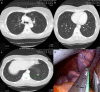

Single-incision thoracoscopic surgery has increasingly attracted public interest and been applied in numerous thoracic procedures. However, single-incision thoracoscopic surgery is associated with requiring subsequent procedures, such as intercostal neuralgia. Herein, we extend the single-port technique of pulmonary metastasectomy through a single subxiphoid approach, and report the first two cases of this procedure to date.